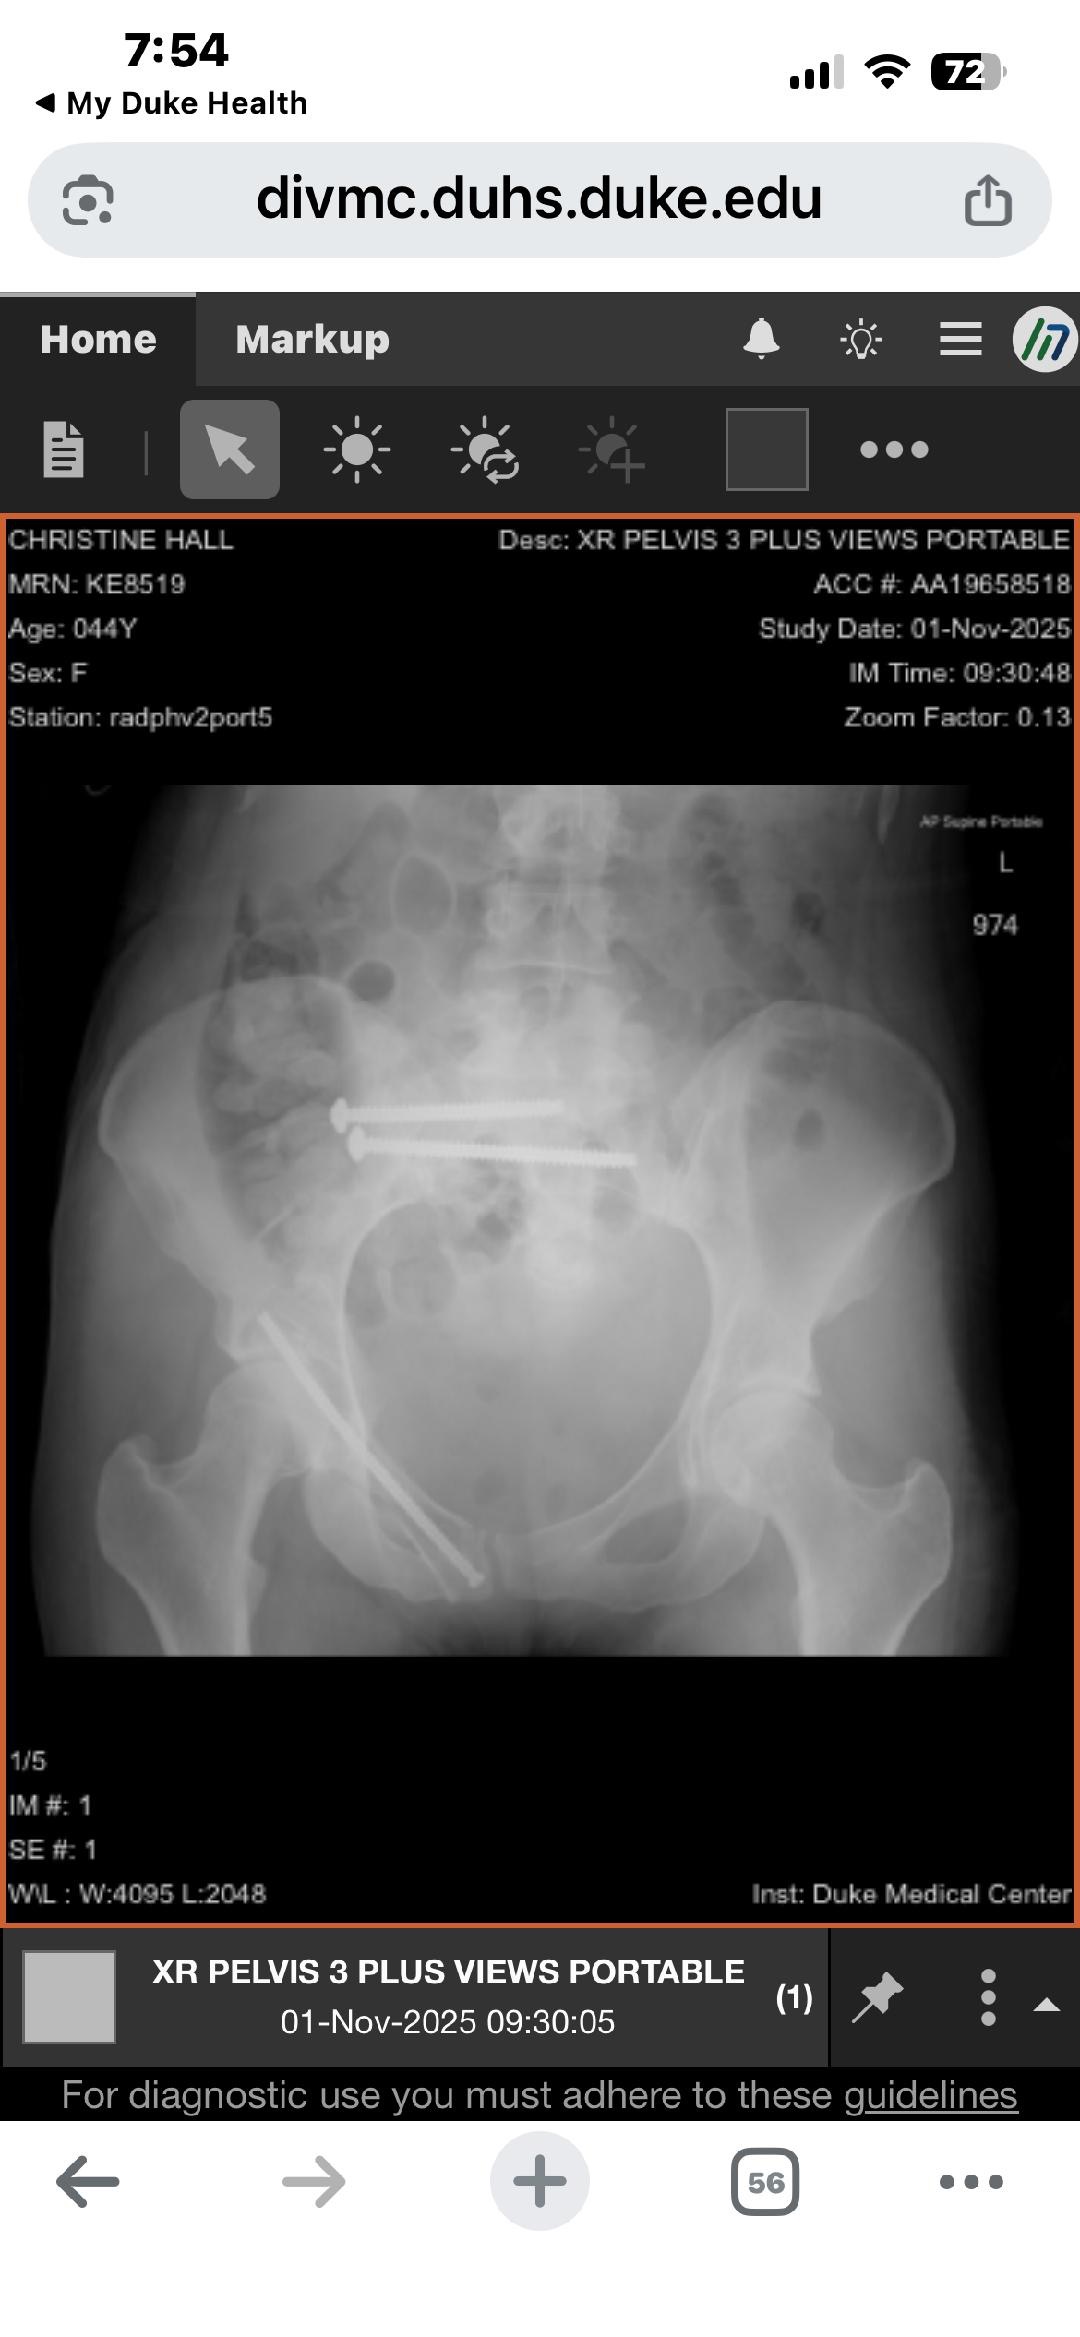

Christine’s injuries, however, were severe. She was airlifted to Duke, where surgeons placed hardware to stabilize multiple fractures in her pelvis and sacrum. Her recovery is expected to take up to a year. She cannot drive, cannot work, and has been navigating this long, painful recovery as a single mom trying to stay strong for her daughters.